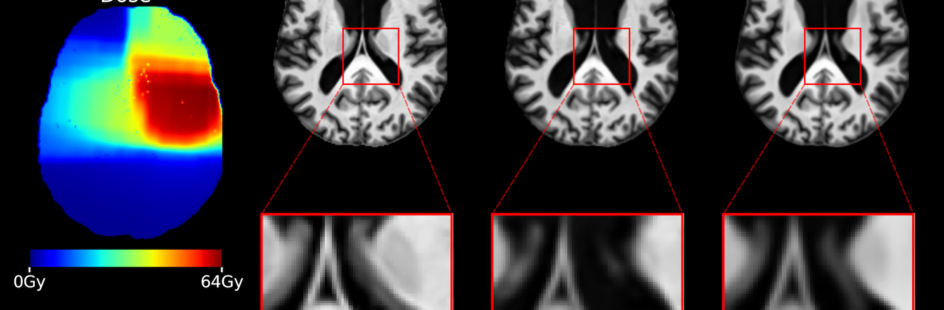

In een figuur toont Selena hoe het AI-model werkt. “Je ziet de MRI-scan van vóór de radiotherapie en de te geven dosis radiotherapie. Op basis van deze data maakt het model afbeeldingen die laten zien hoe de hersenen in de tijd veranderen na behandeling met radiotherapie, bijvoorbeeld na een half jaar of een jaar.”